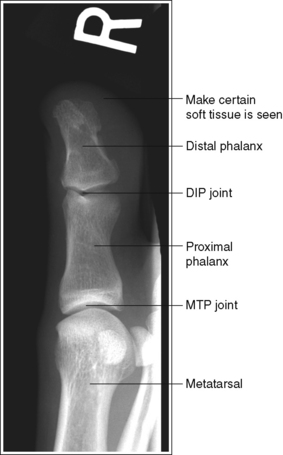

FIGURE 6-1 First AP axial toe projection with accurate positioning. DIP, Distal interphalangeal; MTP, metatarsophalangeal.

The digit demonstrates no rotation. Soft tissue width and midshaft concavity are equal on both sides of the phalanges.